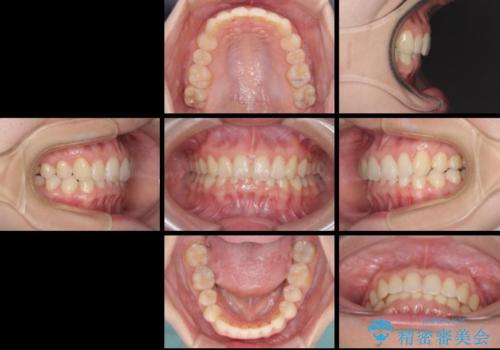

インビザラインによる前歯の矯正治療

- 口元の深い咬み合わせ(ディープバイト)を気にして来院された患者様です。

インビザラインによる上下歯列の遠心移動(後方移動)により、口元のデコボコとディープバイトを改善することとしました。

下顎左右の犬歯とその後ろにある第一小臼歯、計4歯がシミュレーション通りに動かずディープバイトがなかなか改善されませんでした。

マウスピースの再製作を何度か行いましたがうまくいかないため、部分的にワイヤー矯正を併用することを提案しました。しかし、最も気になっていた前歯のデコボコはきれいに改善されたため、これ以上治療を希望されず、治療を終了することとしました。(今後気になった際には再開する予定です)